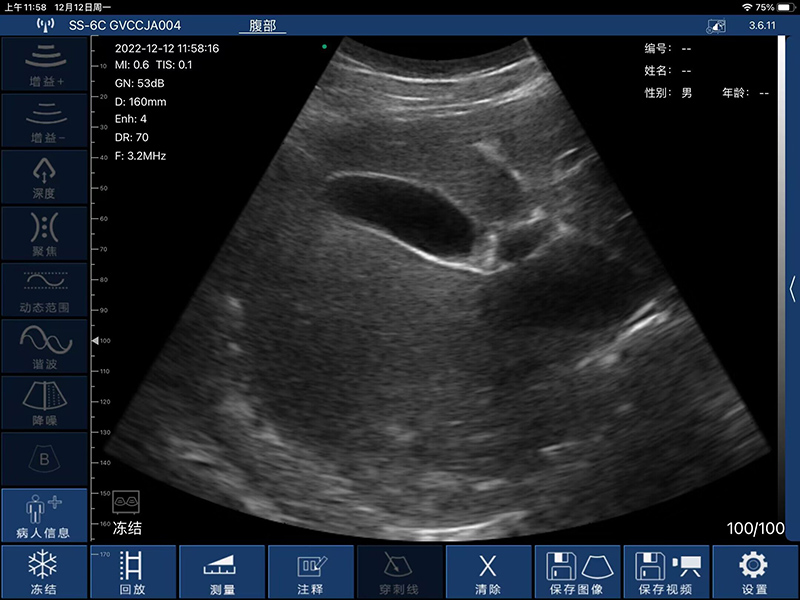

- 扫描深度:90/160/240/305mm,可调

- 显示模式:B、B/M、Color、PW、PDI